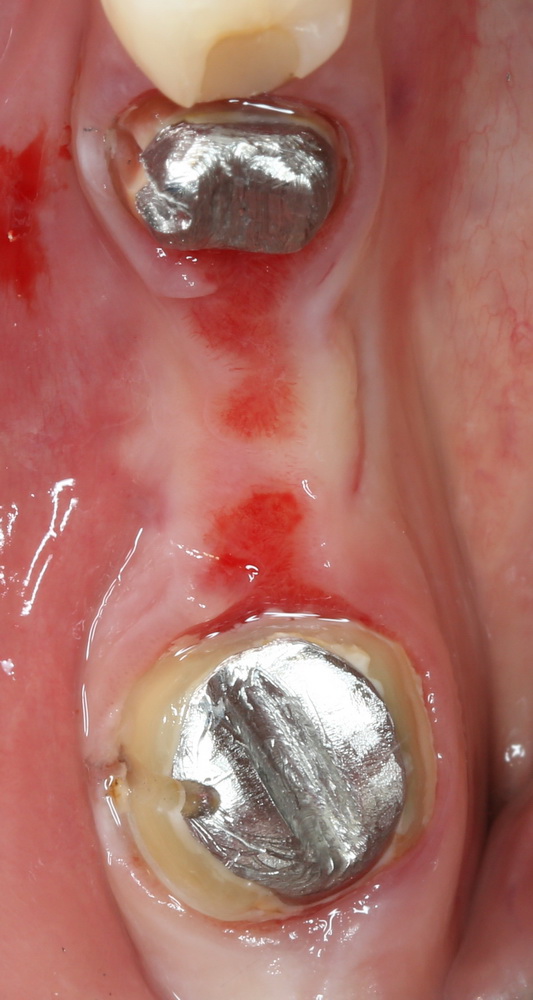

Снимаем коронки, готовим зубы к удалению:

Начинаем с самого сложного — зуба #47:

Гранулема настолько большая, что ее видно из лунки:

Аккуратно ее удаляем. Приходится пожертвовать межкорневой перегородкой:

В лунку помещаем Neocones, Bioss Collagen:

Затем к краям лунки подшивается Mucograft Seal:

Это относительно новый форм-фактор Geistlich Mucograft, специально предназначенный для таких случаев:

После чего можно заняться лункой зуба #45. Там тоже гранулема. Немаленькая:

Которую мы удаляем, а саму лунку консервируем точно по такому же принципу, что и лунку #47 (Neocones, Bioss Collagen):

И «запечатываем» с помощью Mucograft Seal:

Далее — обычные рекомендации после удаления зубов, контрольный осмотр через день:

и через неделю: